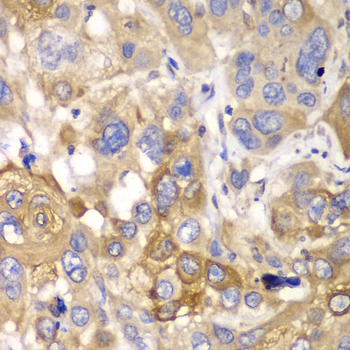

Immunohistochemistry of paraffin-embedded human esophageal cancer using PPP1CB antibody at dilution of 1:100 (400x lens).